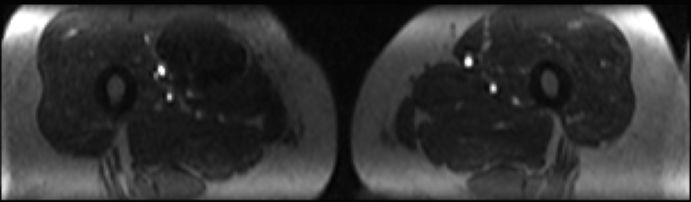

| Oberschenkel | 49-jährige Frau mit einem myxoiden Liposarkom der rechten Adduktoren-Loge.![]() |

Die enge Lagebeziehung zur A. femoralis ist gut erkennbar.![]() ![]() |